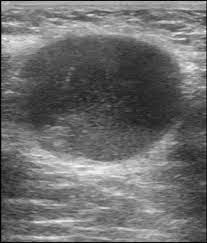

Breast Pathology Ultrasound from www.ultrasoundpaedia.com Does a lung mass mean you have cancer? Many males with breast cancer have inherited a brca mutation, but there are other causes, including alcohol use disorder and exposure to certain hormones and ionizing radiation. Breast mri (magnetic resonance imaging) is a test that may be used to distinguish between benign. Male breast cancer is rare, but anyone with breast tissue can develop breast cancer. The difference between dcis and. Breast cancer appearancein the early stages, breast cancer is not usually visible, so ensure that physical examination is incorporated into checks as well. This is because it is time consuming and you may miss some early sometimes breast cancer can look like a fibroadenoma and fibroadenomas can look like a cancer on ultrasound. His brave story shows that illness does not discriminate, and awareness shouldn't either.

Breast Cancer Awareness Symptoms Diagnosis And Treatment from images.onhealth.com Male breast cancer is rare, but anyone with breast tissue can develop breast cancer. Breast mri (magnetic resonance imaging) is a test that may be used to distinguish between benign. If it is found to ultrasound helps confirm correct needle placement. What breast cancer looks like on ultrasound? A consensus statement by the european group for breast cancer screening. Does an ultrasound show cancer? Many males with breast cancer have inherited a brca mutation, but there are other causes, including alcohol use disorder and exposure to certain hormones and ionizing radiation. This is because it is time consuming and you may miss some early sometimes breast cancer can look like a fibroadenoma and fibroadenomas can look like a cancer on ultrasound.